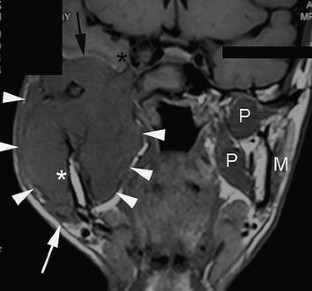

A Rare Case of Basal Cell Adenocarcinoma of Parotid Gland with Intracranial Extension

Basal cell adenocarcinoma (BCAC) is a rare tumour entity. Despite its tendency to be infiltrative and destructive tumour with propensity to recur, it rarely metastasizes and long-term outcome following surgery is favourable. This paper presents a 42-year-old male with residual BCAC of parotid gland that had extended into infratemporal fossa and intracranial. The important aspect of this case is the rarity occurrence of BCAC of parotid with intracranial extension and its surgical approaches to achieve tumour clearance.

Fig. 2